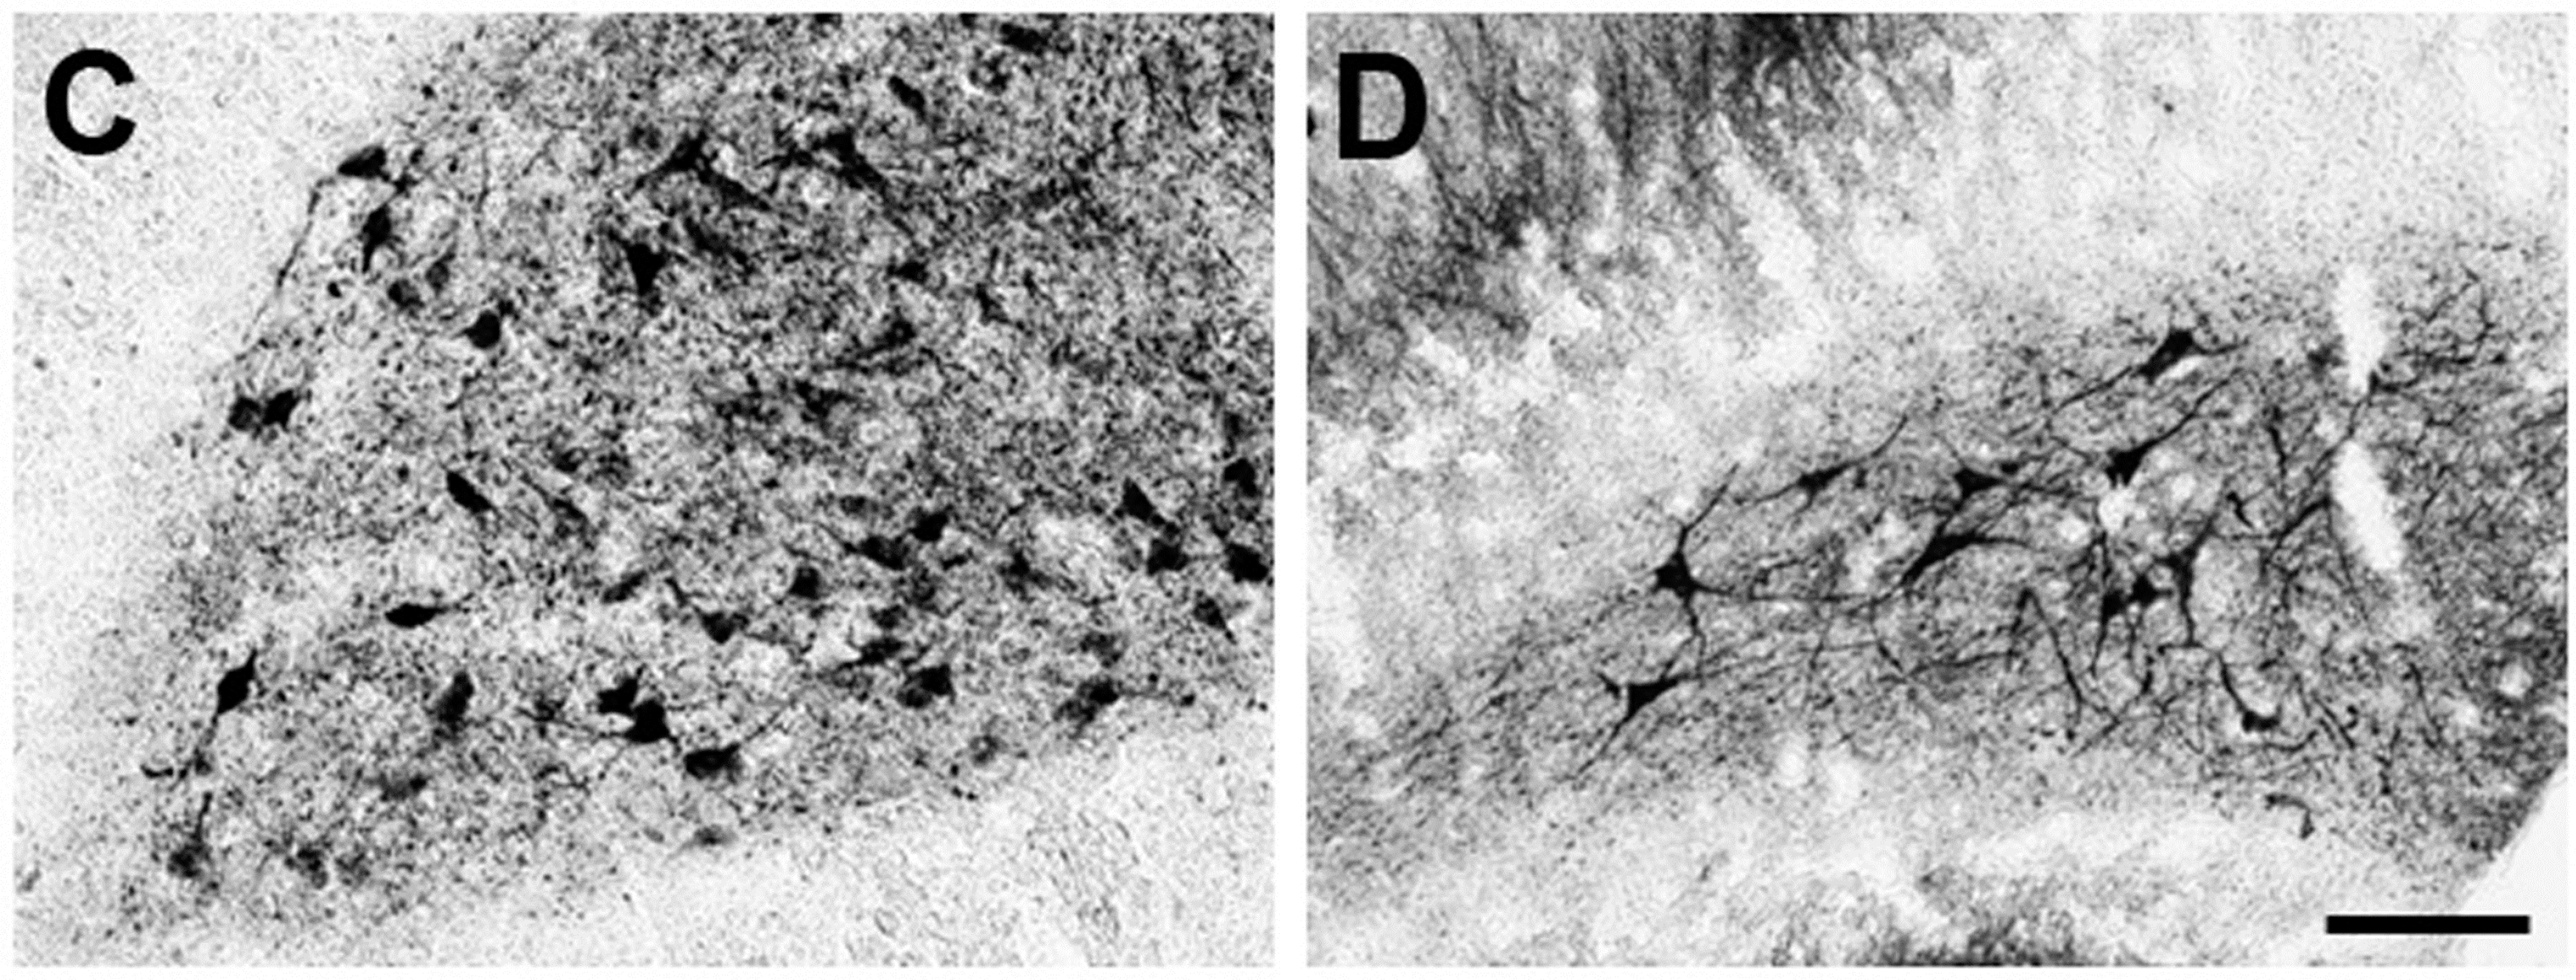

Previously it was demonstrated that MEL increases dendritogenesis in adult interneurons of the hilar region of the hippocampus and in new neurons formed in the dentate gyrus of rodents [17,18]. Also, it was shown that activation of CaMKII is involved in dendrite formation and maturation [23,44]. Thus, we tested whether the KN-62 compound, a specific inhibitor of CaMKII, suppresses the MEL effects on organotypic hippocampal cultures. As shown in Figure 1A, in presence of the vehicle, neurons of triangular shape with thin dendrites were evident. In presence of 100 nM MEL, neurons developed an intricate web of dendrites (Figure 1B). By contrast, hippocampal slices incubated with the CaMKII inhibitor and the vehicle, showed few and thin dendrites in the interneurons of the hilar zone (Figure 1C), while in hippocampal slices incubated with KN-62 and 100 nM MEL, only triangular and bipolar neurons with short and thin dendrites were evident and the complex dendrite network elicited by the indoleamine was not observed (Figure 1D). Since MEL-induced dendrite formation was abolished in the presence of the CaMKII inhibitor, data indicate that the enzyme participates in the mechanism by which MEL elicited dendritogenesis.

Effect of Ca2+/CaM-Kinase II on dendrite formation elicited by Melatonin. Participation of CaMKII on dendrite formation elicited by MEL was evaluated by specific inhibition of its activity with KN-62. Thus, rat brain hippocampus was cut in 400 µm slices and cultured in Neurobasal® (GIBCO by Life Technologies, Grand Island, NY, USA) media for 7 days. Then they were incubated for 6 h with either the vehicle (A); 100 nM MEL (B); or pre-incubated with 10 µM KN-62 (C,D) followed by 6 h incubation with the vehicle (C) or 100 nM MEL (D). After the incubation time, slices were cut into 50 µM sections and immunostained for the specific marker of dendrites MAP2. Afterwards, slices were incubated with a secondary antibody coupled to biotin-avidin-peroxidase. Images were acquired with a digital camera coupled to a light microscope with the NIS-Elements software. Scale bar = 100 µm.